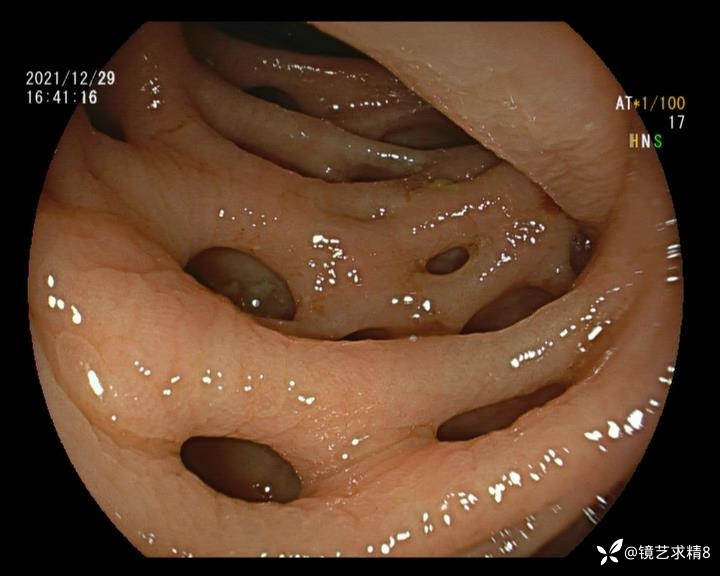

结肠内违建⥤结肠多发憩室☞续

小壮兵爱学习等 2人推荐看到手机存有2年前一个病例仅有的3张图片,因为没有更多的图片就只描述了多发憩室这个内容,没想到浏览量很快上万,很多都和我一样第一次见这么多憩室的结肠,就不得不想要把2年前所有的片子拷贝出来分享。该病例憩室合并外源性因素成为憩室出血的原因。后面附有代表性的全结肠图片。

患者以消化道出血入院,胃镜未见异常,肠镜进入乙状结肠就看到很多憩室,同时还看到肠腔用清肠药后移动下来1枚尖锐的枣核,这么多憩室,这个枣核扎入憩室的机会非常大,推测应该是掉入一坑🕳就算出来还会有很多坑🕳🕳🕳等着,掉入憩室内很容易刺破血管,这可能就是消化道出血的原因,继续前进可以看到有一些憩室内翻,还有一些息肉,问题来了,那么多憩室,犯罪分子是抓住了,它在那些憩室内作过案?到达回盲部后挨个冲洗,但憩室大小又不足以把镜头进入憩室内观察,针对有血块的憩室冲洗后可疑出血的以夹子闭合或套扎,取出枣核,如果有锥形透明帽可能钻入憩室精准电凝效果更好,若内镜下操作失败介入治疗成功率更高,经内镜下治疗后观察未再出血出院。

亚洲人群结肠憩室主要发生在右半结肠,然后随着年龄的增长而延伸到左半结肠和双侧结肠。相比之下,欧美人群80%的结肠憩室好发于左半结肠,其中乙状结肠憩室占 70%,而大多是假性憩室。 然而,与憩室炎主要发生在左半结肠不同,东西方人群的憩室出血均主要发生在右半结肠,可能与右半结肠的憩室更宽大及憩室血管更易受到损伤相关。